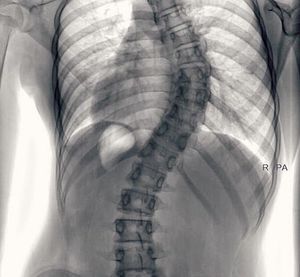

What is yours diagnosis?

Situs invertus + scoliosis ! Look At the heart and the stomac !

Look at your markers. This is a posterior view

Severe scoliosis